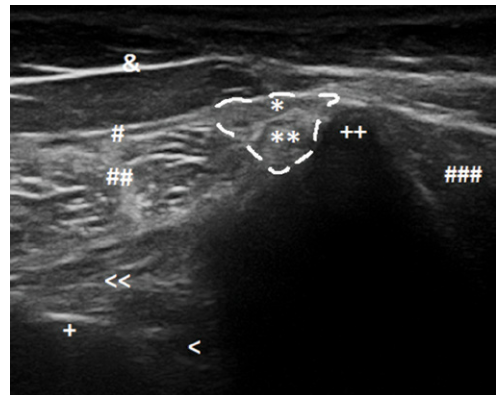

척추기립근이 골반에 붙을 때 단순히 살이 붙는 게 아닙니다. 1. 근육의 겉을 싸고 있는 척추기립근 건막(Aponeurosis) 2. 그 속에 숨어 있는 심부 힘줄(Deep tendon) 이 두 가지 구조물이 골반 뼈에 와서 붙는데요.

DOI: 10.4103/jrms.JRMS_1034_18 피부 가까이에 있는 겉에 있는 건막과 속에 있는 힘줄이 겹쳐져 있어서 정확히 어디가 고장 났는지 보지 않고는 알기가 어렵습니다. * * * 3. 왜 초음파로 봐야 할까요?

DOI: 10.15557/JoU.2018.0003 2018년 Journal of Ultrasonograph의 연구에 따르면, 건강한 사람의 이 부착부는 초음파상 하얗고 매끄러운 섬유 다발로 보입니다.

DOI: 10.15557/JoU.2018.0003 하지만 통증이 있는 환자의 경우 다음과 같은 변화가 관찰됩니다. 1. 부착부 비후: 힘줄이 퉁퉁 부어 두꺼워져 있거나, 2. 저에코 병변: 염증으로 인해 어둡고(Hypoechoic), 3. 골극 형성: 뼈 표면이 울퉁불퉁하게 튀어나와 있습니다.

DOI: 10.15557/JoU.2018.0003 더 중요한 이유가 있습니다. 이 장골능 주변에는 '상둔피신경(Superior Cluneal Nerve)' 이라는 예민한 신경이 지나갑니다. 눈으로 보지 않고 주사를 놓다가 자칫 이 신경을 건드리면 찌릿한 통증이 발생할 수 있죠. 초음파를 사용하면 이 신경과 혈관을 피해 시술할 수 있습니다. * * * 4. 한의 영상학의 핵심:경혈과 해부학의 만남 자, 그렇다면 한의학에서는 어떻게 치료에 적용할까요? 한의학의 초음파 가이드 시술은 '경혈'의 해부학적 구조를 타겟팅하여 유착을 풀어내는 데 집중합니다.